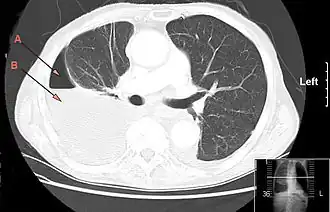

Компьютерная томография, демонстрирующая массивный правосторонний гидропневмоторакс, обусловленный эмпиемой плевры. Стрелка A: газ, B: жидкость